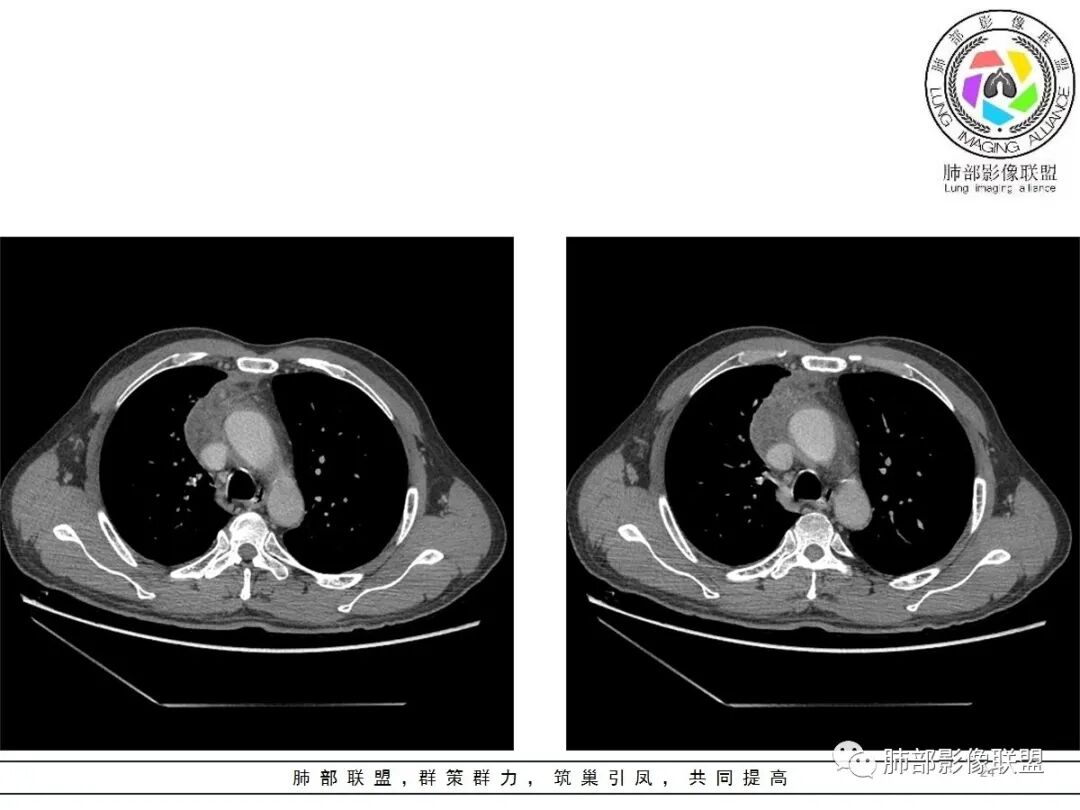

小赵:这个是3月15日的视频

小赵:第二个是3月19日的视频

周围脂肪间隙密度增高,内部小点状很低密度影

右侧少量胸水

19日,4天后, 内部低密度影有,周围渗出增多,胸水增多

2.胸膜掀起,右侧内乳动脉略增粗,定位右前上纵隔内占位。

3.右上纵隔囊实性占位,边界清楚。中央见点状脂肪密度影,边缘见一点状钙化影,增强不均匀环形强化。

4.四天内病灶变化快,块影增大且不规则,包膜似不完整,边界不清,上份可见浸润或渗出,与周围心脏大血管及心包等间隙不清。胸水增多。

5.未见明显淋巴结增大

第一次的检查符合胸腺瘤影像学改变,短期内的形态学改变及突然出现的边界模糊或浸润等,符合出血或炎症。